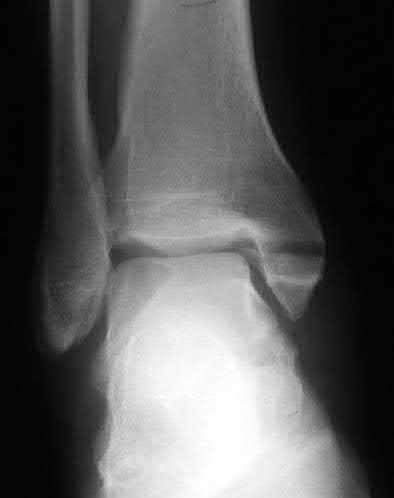

A 28-year-old male sustains a severe hyper-dorsiflexion injury to his ankle in a motor vehicle accident, resulting in a Hawkins Type III talar neck fracture. Which of the following arteries provides the predominant blood supply to the body of the talus, placing it at significant risk for avascular necrosis in this injury?

Options:

- Artery of the sinus tarsi

- Anterior tibial artery

- Dorsalis pedis

- Artery of the tarsal canal

- Peroneal artery

Correct Answer: Artery of the tarsal canal

Explanation:

The artery of the tarsal canal, which is a branch of the posterior tibial artery, provides the dominant blood supply to the talar body. In a Hawkins Type III fracture (talar neck fracture with subtalar and tibiotalar dislocation), the blood supply from the artery of the tarsal canal, the artery of the sinus tarsi, and capsular vessels are disrupted, leading to an avascular necrosis (AVN) rate approaching 100%.